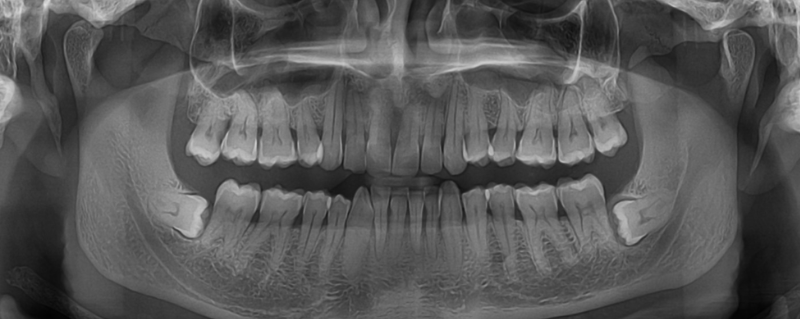

Dental diagnostic techniques use digital imaging and advanced scanning tools to examine teeth, gums, jawbone, and surrounding oral structures. These tools help detect hidden dental problems that cannot be seen during a normal dental check-up.

- Tooth decay and cavities

- Root infections

- Gum disease and bone loss

- Impacted or missing teeth

- Jaw and bite problems